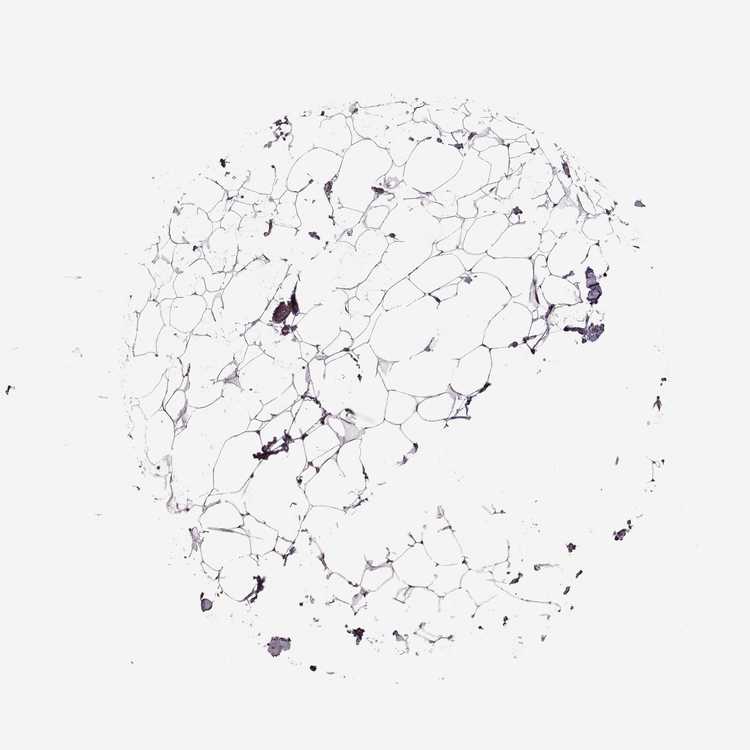

SOFT TISSUE 1 - Antibody stainingi

Antibody staining in the annotated cell types in the current human tissue is reported as not detected, low, medium, or high, based on conventional immunohistochemistry profiling in selected tissues. This score is based on the combination of the staining intensity and fraction of stained cells.

Each image is clickable and will lead to virtual microscopy that enables deeper exploration of all samples and also displays staining intensity scores, fraction scores and subcellular localization as well as patient and tissue information for each sample.

Antibody HPA034631Antibody HPA071347Antibody CAB033265Antibody CAB037325

Chondrocytes -Low--

Fibroblasts HighNot detectedNot detectedNot detected

Peripheral nerve Medium-MediumNot detected